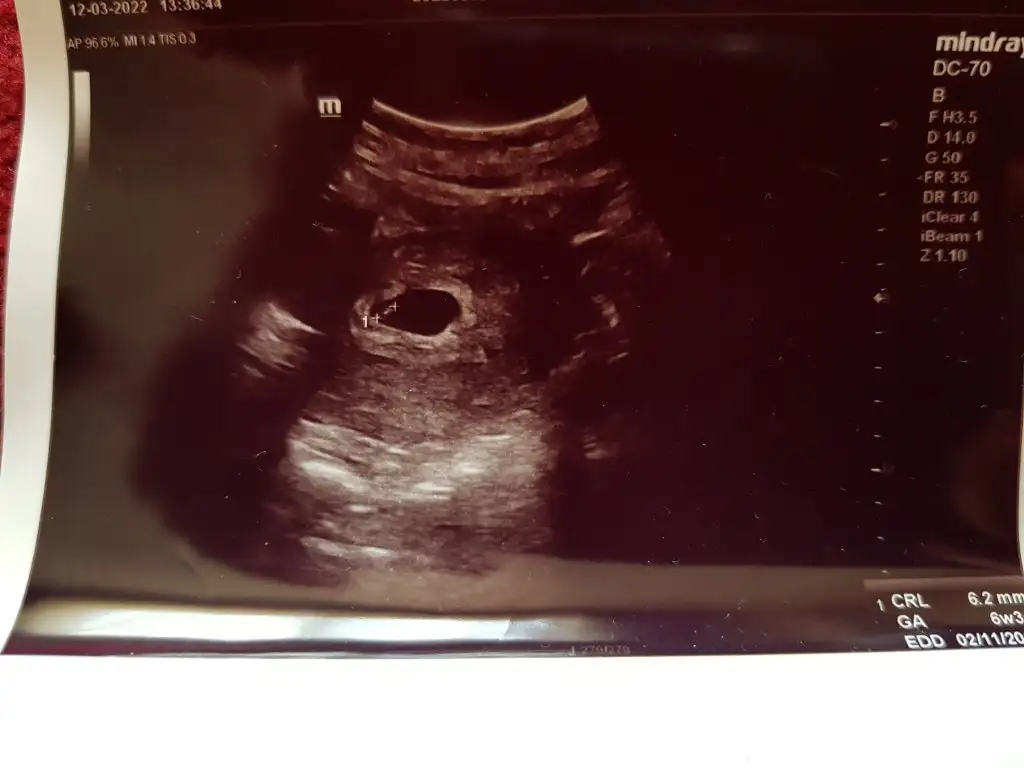

3.foto 6+3